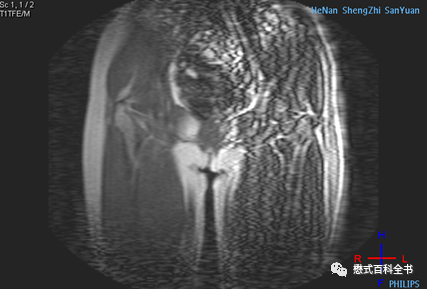

图3~5:Ghosting伪影的表现

一般Ghosting伪影产生的原因主要是硬件系统不稳定导致的。比如:射频系统不稳定、梯度系统不稳定、磁场均匀度等。

Ghosting伪影的图像表现是在相位编码方向出现多个连续的重影(幽灵样影像),这种连续的多个重影还是比较好识别的。